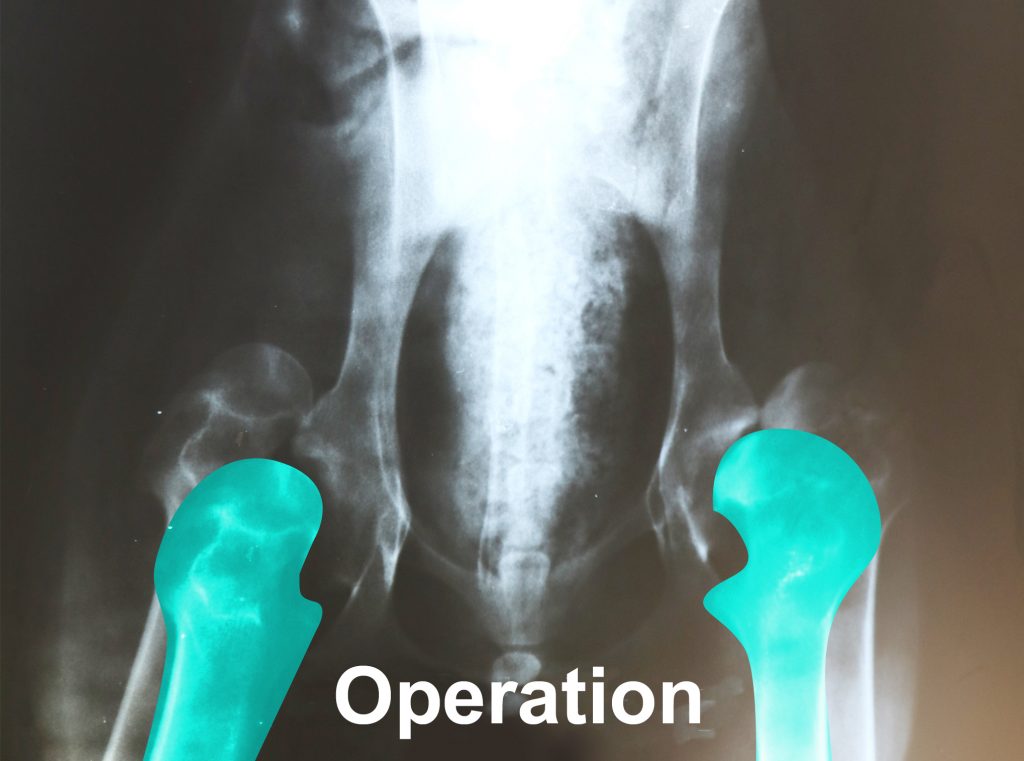

Randy’s operation will reposition his thigh bones to fit into the hip sockets correctly (noted with the colored bones).